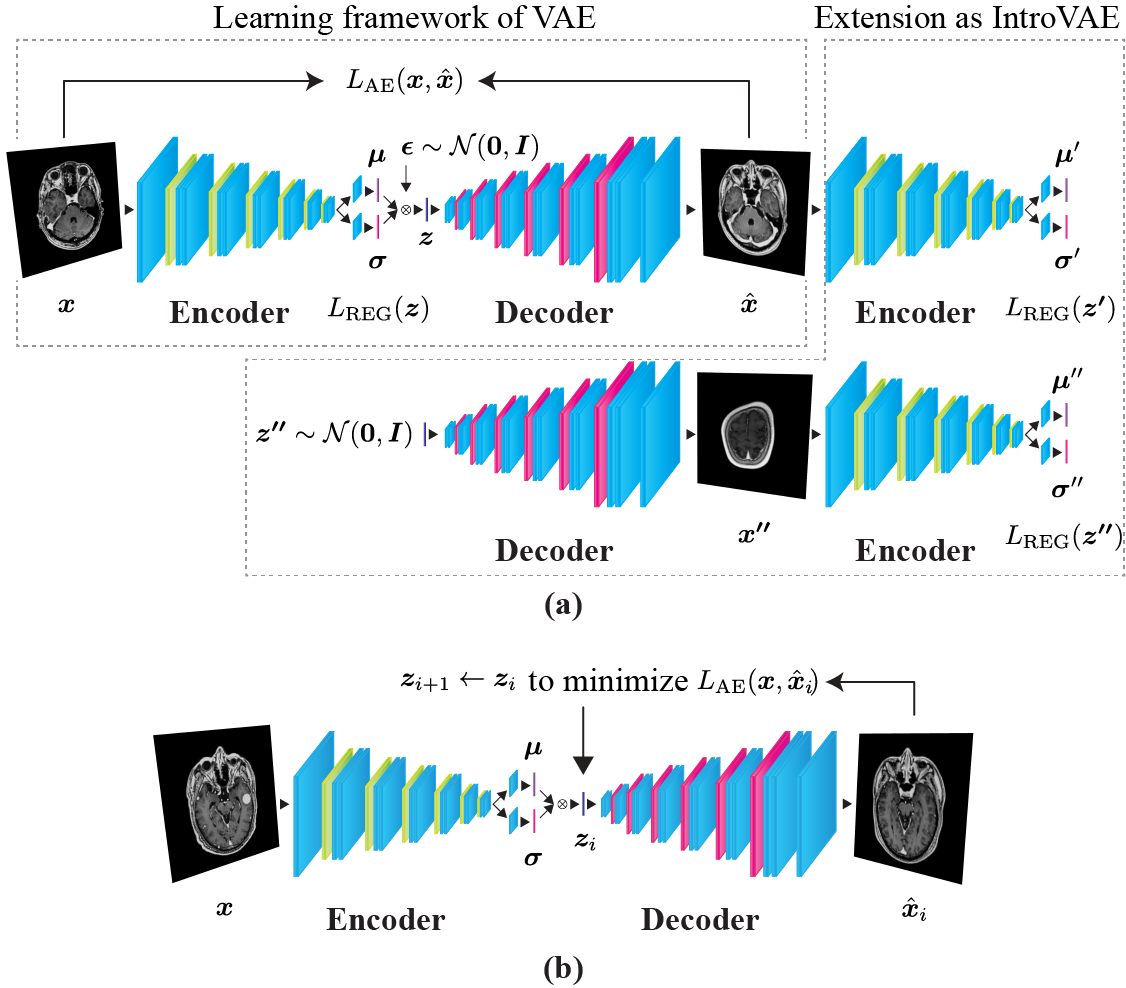

To construct a low-dimensional manifold representing image-level normal brain anatomy, we exploited a VAE as the basic architecture for the image reconstruction network. Subsequently, we utilized IntroVAE as an extension of the VAE as well as for latent representation searching to enhance the anatomical fidelity of the reconstructed images (Fig. 1).

II-B2 Introduction of IntroVAE

We utilized IntroVAE [5], which is an extended architecture of the VAE. By introspectively self-evaluating the differences between the input and reconstructed images, IntroVAE can self-update to synthesize more realistic, high-resolution images. It is noteworthy that a min–max game exists between the encoder and decoder, similar to that employed in GANs. The encoder is trained to determine whether the input images are from a data distribution or the decoder , whereas the decoder is encouraged to “fool” the encoder by generating realistic images.

In the learning framework of IntroVAE, is extended as an adversarial cost function. The encoder is trained to minimize for real images to match the posterior to the prior , and conversely, to increase for the generated images such that the posterior deviates from the prior . Hereinafter, specifically indicates that the latent variables originate from the generated images . Furthermore, the decoder attempts to generate realistic reconstructions based on latent variables such that the encoder mistakenly assigns a small value to the generated images. The regularization term (3) is changed as follows:

| (4) | ||||

and

| (5) |

where , is a scalar of the positive margin, and . When is positive, the equations above prompt a min–max game between the encoder and decoder. Finally, the overall objectives are described as follows:

| (6) |

| (7) |

where and are weighting parameters that balance the importance of each loss term.

II-B3 Latent Representation Searching

We further applied latent representation searching to improve the latent representation for achieving a better reconstruction (Fig. 1b), as inspired by the method used in AnoGAN [16]. To obtain the optimal latent representation , the method begins with the first latent position , which is initially mapped by the encoder capturing the input images . Subsequently, is input into the decoder to yield the first reconstructed images . Using the reconstruction error for the residual between and , the latent representation can be updated based on the gradients for objective minimization, shifting to a better position in the latent space. Subsequently, the deviation of the secondary reconstructed images with respect to is evaluated for the next objective. This update rule is described as an iterative process from to to minimize . After sufficient training steps of this optimization process, we can expect to yield a better image reconstruction .